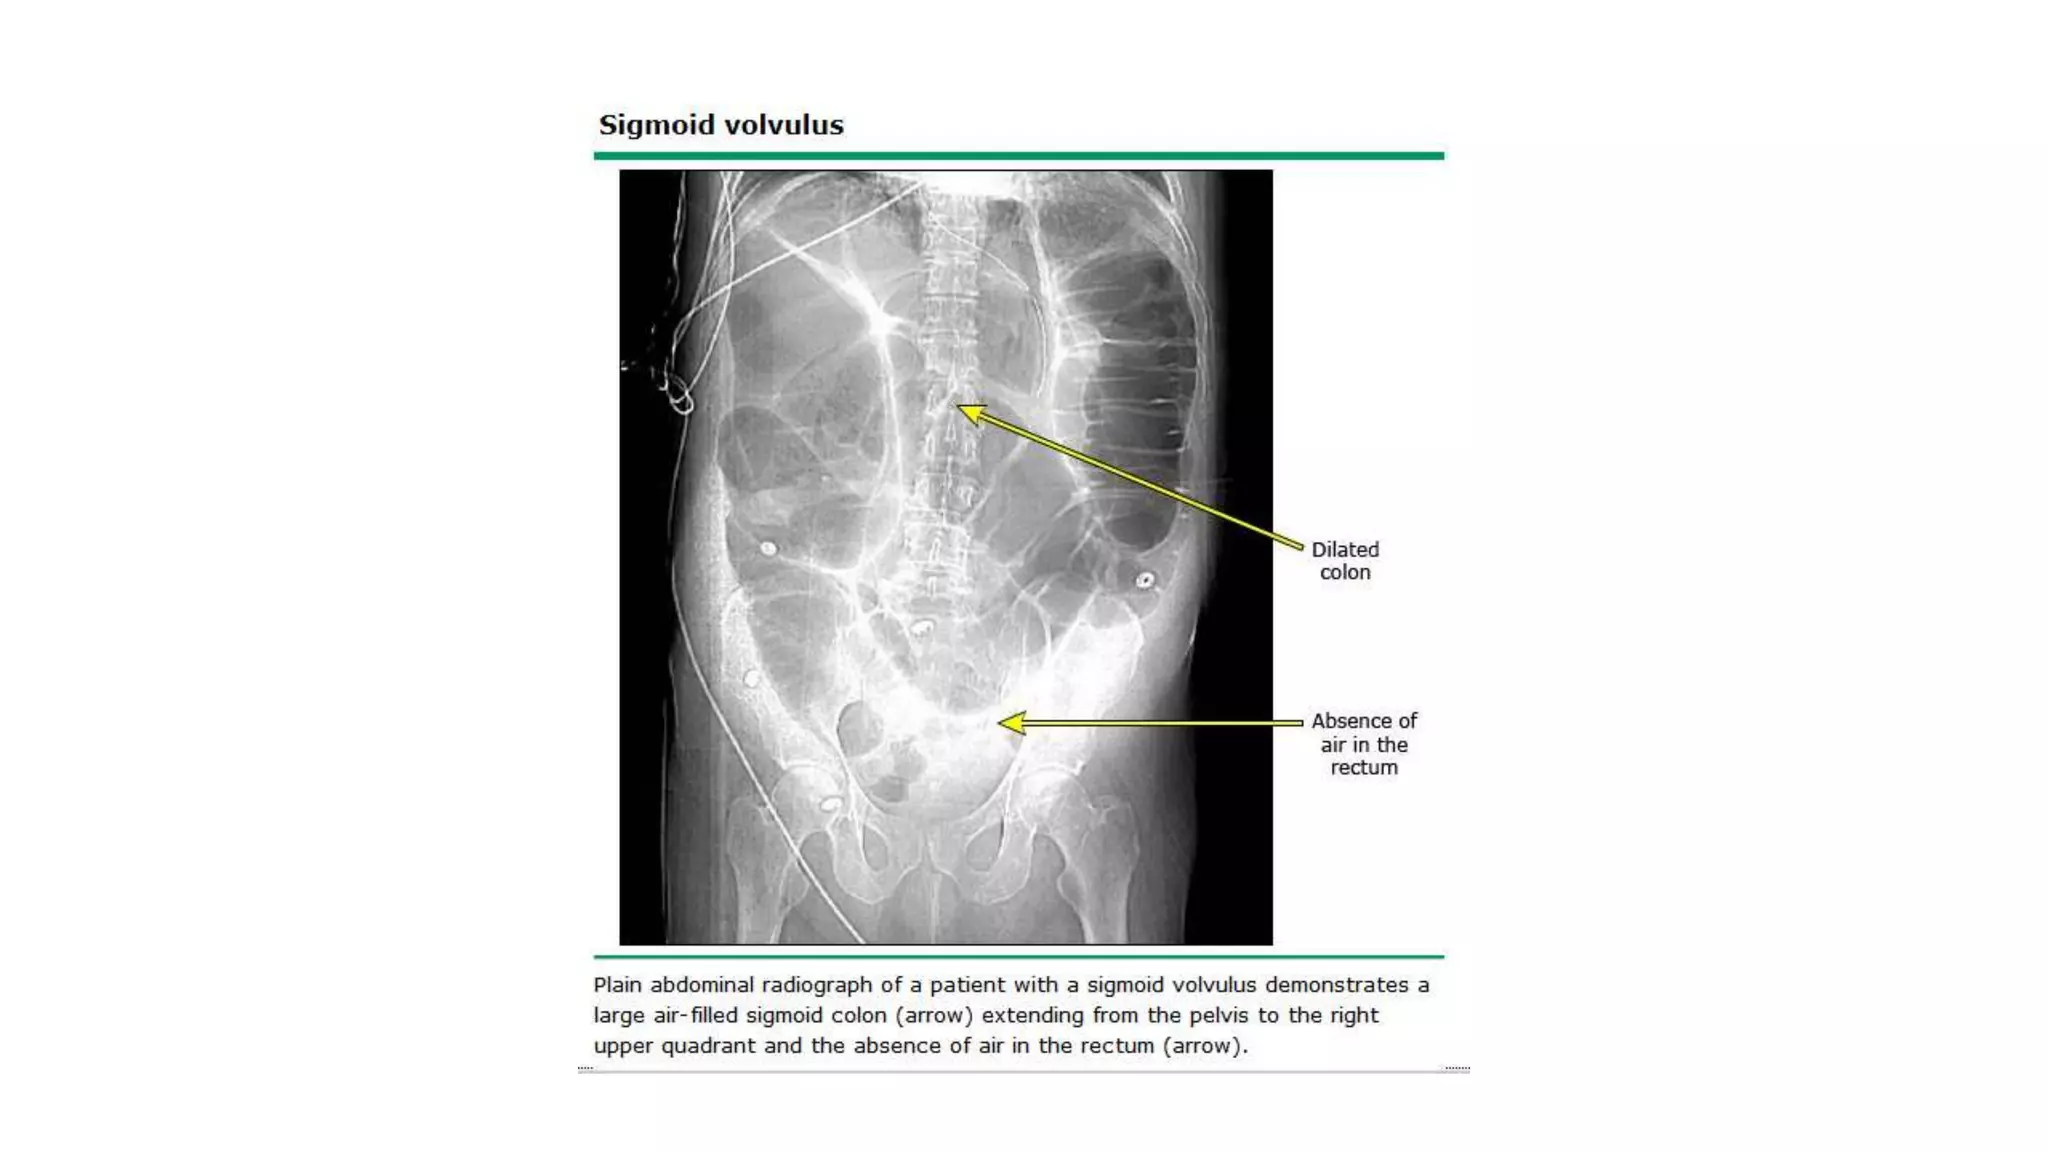

Radiological features in large bowel obstruction

• Colonic distension usually visualized in the periphery

• show the hustrations of the Taenia Coli.

• absence of rectal air and air fluid level if ileocecal valve incompetent

• May also demonstrate the cause of obstruction (volvulus)